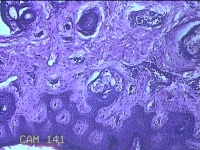

性别

男

年龄

23岁

临床诊断

右耳部肿物

一般病史

右耳前无痛性肿物20余年。

标本名称

大体所见

灰白暗红色肿物0.7x1.5x0.2cm一个,表面糜烂。

图3